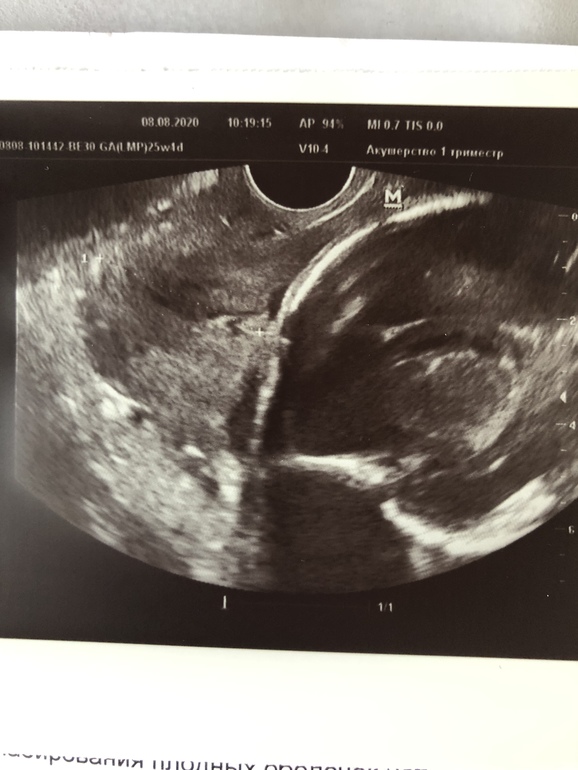

Для своего спокойствия хожу на цервикометрию. Результат сегодня по заключению приемлемый: 25+4 нед, 33,7 мм, все закрыто, воронок нет и др. А вот на приложенном к заключению фото уже дома я увидела нечего странное. Какое-то непонятное вкрапление перед пузырем. Что это может быть, пробка что ли?..

См. у крестика, который справа